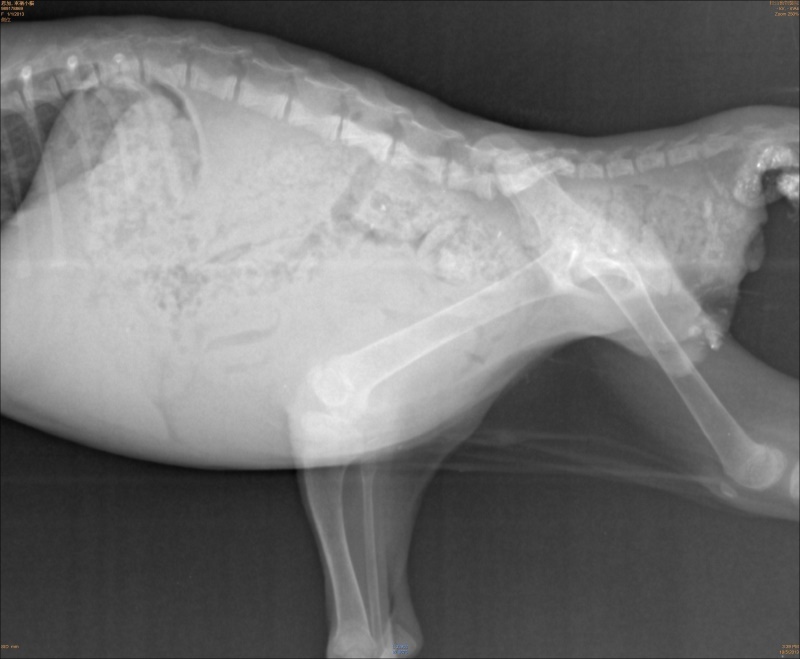

主題: 後肢癱瘓路倒貓 申請者姓名: 岳丹楓 花色: 申請日期: 2013-12-19 20:33:41 申請者部落格: 申請者臉書網址: 所在縣市/合作醫院: 台北市/恩加動物醫院 治療費用: 5700元 需求人數: 13人 已結案 (2014-01-10 17:45:21) 報名人員: Jye Lin x2(已付款)、Jocelyne YuYu Kao x4(已付款)、姆姆媽 x2(已付款)、megumi(已付款)、李仲石 x4(已付款)、 候補人員: 動物病情說明: 一隻在外面路邊爬行的小貓,民眾通報捕捉,送醫檢查為下半身癱瘓,並且積了許多糞便,於是灌腸通便擠尿治療,後肢拖行摩擦破皮有一些小傷口,每天醫師幫小貓擠便和擠尿並給予幫助神經恢復的藥物,經過兩周治療不見改善,狀況穩定,尚未找到可以幫忙照顧的中途,先自費住院,請醫師代為照顧,貓咪驅蟲除蚤後便便正常已經施打預防針(這都是自費),最近找到人可以幫忙,已經先出院,轉由中途照顧,當時的醫療費用還請各位幫忙。